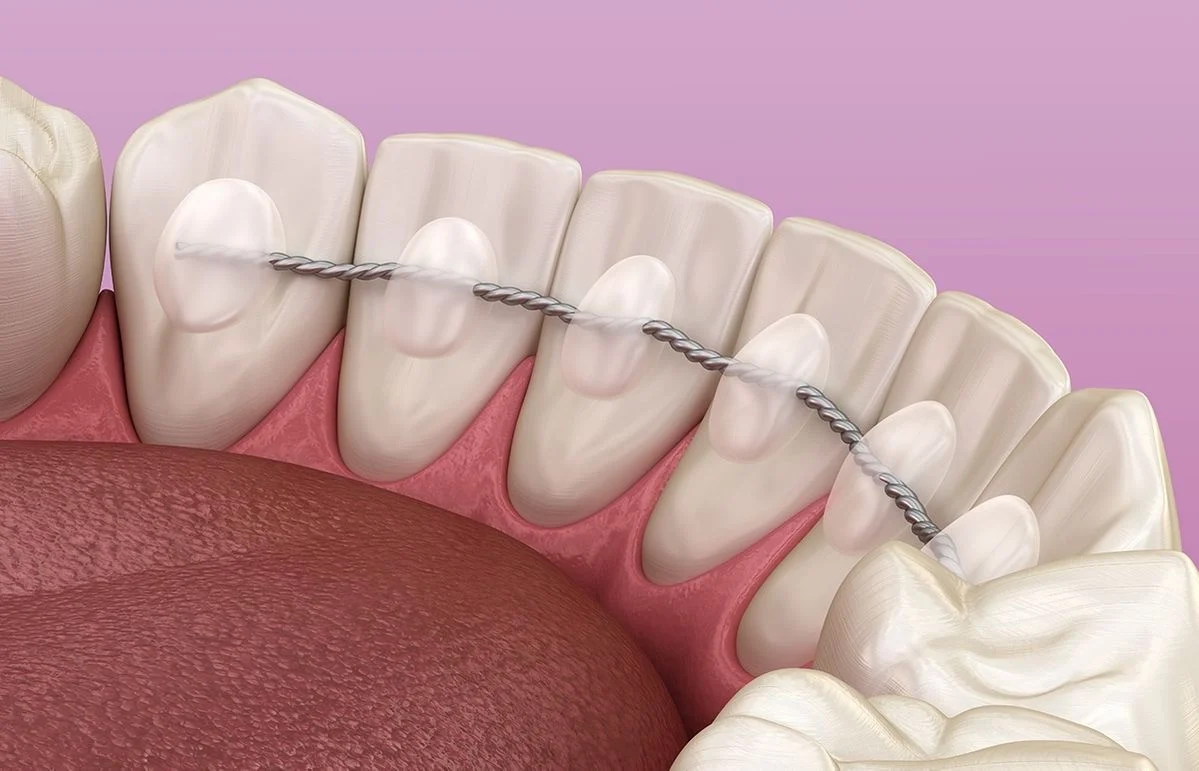

Ortodontske aparate delimo na mobilne i fiksne.

Mobilni aparati su primereni našim najmlađima, da bismo im na vreme odnosno pre formiranja korena zuba, uskladili zubne odnose i blagovremeno sprečili pojavu anomalija položaja zuba.

Fiksni aparati nemaju starosnu granicu, sastoje se od bravica i žičanih elemenata, mogu biti metalni ili estetski (keramički), postavljeni sa prednje ili unutrašnje strane zuba.

U zavisnosti od stepena ortodontske nepravilnosti i starosne dobi, od nas ćete dobiti adekvatan plan terapije.